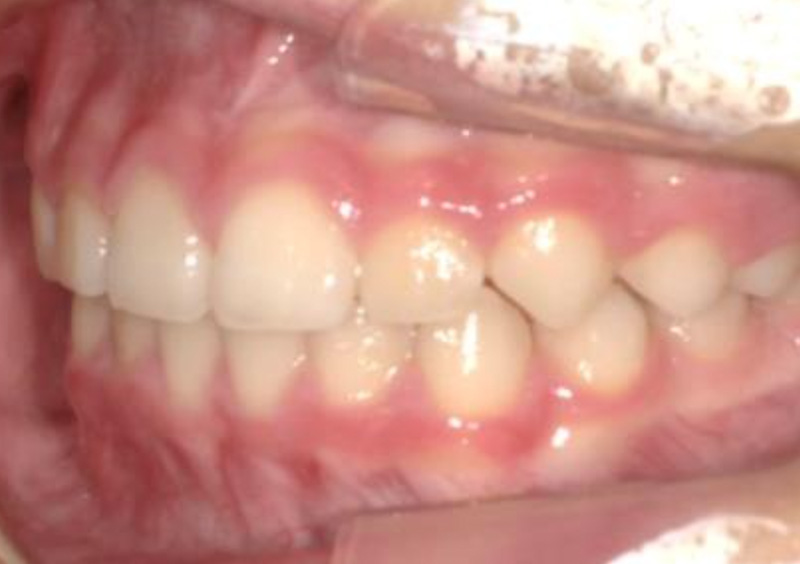

子供の矯正治療 大人の歯が生えてくるスペースがない 2026.03.19 【プレオルソ】大人の歯が生えてくるスペースがない 治療前 治療後 担当医 一瀬 悠依華 先生 主訴 大人の歯が生えてくるスペースがない 期間 4年 費用 35万円(小児矯正) 治療内容 プレオルソ 治療に伴うリスク 歯根吸収、歯肉退縮 関連症例